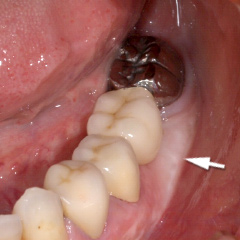

1.銀歯の周りに歯周病が進行してます。

2.根と根の間の骨が溶けて穴になってます。

3.術後7ヶ月、骨の再生が認められます。

4.厚い歯肉を作り、セラミックで修復しました。

| 清掃性の良くないブリッジを外した状態。 | FGGを行い、清掃性を改善した状態。 |